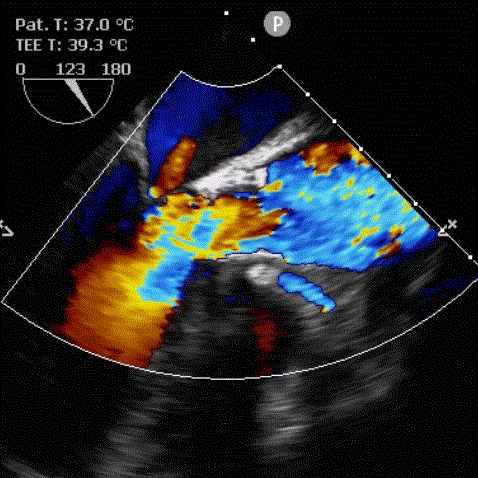

患者女性,75岁,因“反复胸闷、胸痛1年余”入院。超声心动图示主动脉瓣重度狭窄钙化,伴中重度关闭不全。CT显示主动脉瓣为Type 1型二叶瓣,且无冠瓣与左右冠瓣融合嵴形成“T型”钙化结构,属TAVI挑战病例。瓣环平均直径22.5mm,瓣环面积402.0mm²。左冠脉开口高度11.8mm,右冠脉开口高度11.0mm。术前TEE示峰值流速4.9m/s,平均跨瓣压差54mmHg,有强烈手术指征。

9月27日上午10时,直播开始,魏来教授团队耗时约1小时,经右侧股动脉植入23# Renatus介入主动脉瓣。瓣膜植入位置理想,功能表现出色,造影及经食道超声观察显示瓣膜无中央性返流,轻微瓣周漏,无冠脉血流受阻,无传导阻滞,主动脉瓣峰值流速降至2.0m/s,平均跨瓣压差降至7mm/Hg。手术取得圆满成功。

术前心脏彩超                               术后心脏彩超